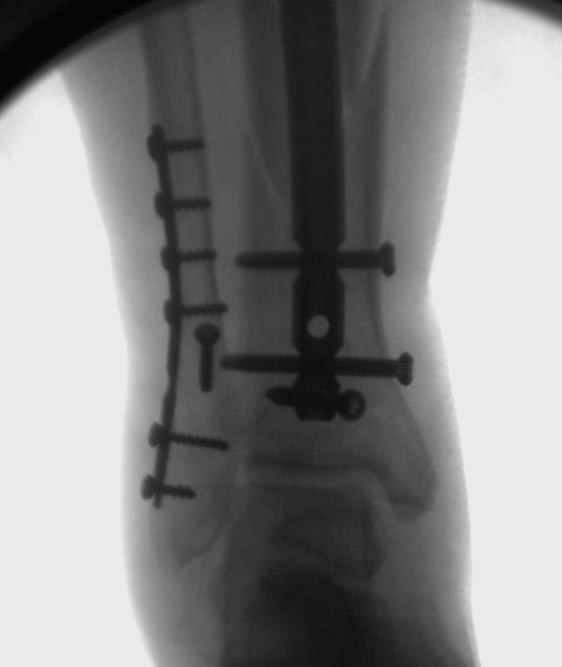

спрашивает что делать с больным который поступил недавно, фермер 55 лет падение при пьяной драке в баре, года два назад перенес операцию на лодыжке, на снимках и КТ перелом без вовлечения сустава,

Повреждение такой локализации, на которой применимы и аппарат (классический Илизарова или гибридный), пластина, особенно Locked Plate, и гвоздь с блокированием. В нашей клинике был бы выполнен закрытый интрамедуллярный остеосинтез. Желательно использовать гвоздь с возможностью провести более чем 2 обычных фронтальных винта в дистальном отломке.

Здесь мы использовали новый Synthes Nail с дополнительными дырками, в проксимальной части 4: по две косых и поперечные (один стандартный а другой динамический), в дистальной части две поперечные, прямая и косая. Вес больного более 120 кг, нагрузку начнем через месяц.

Получилось красиво, поздравляю. Вверху можно было ограничиться одним винтом во фронтальное статическое отверстие, зачем два 45-градусных?

При такий спирали задний край tibia может быть сломан - нет ли этого в данном случае? На всякий случай можно было ввести 1-2 винта 4,5 мм спереди назад мимо гвоздя. Хотя самый дистальный блокирующий винт, возможно, зацепил этот отломок. А какой тут диаметр гвоздя и locking винтов?